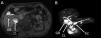

Gastroenterología y Hepatología (English Edition) Septated gallbladder

Septated gallbladder

Figures (2)